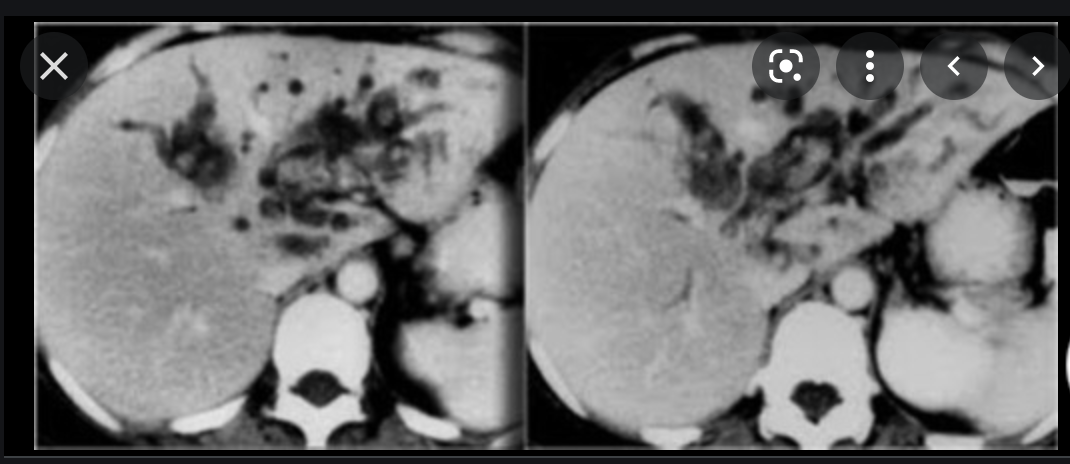

sclerosing cholangitis

- Chronic inflammatory process of intrahepatic 20% and extrahepatic 80% bile ducts that causes progressive narrowing.

- Chronic or intermittent obstructive jaundice is evident.

- Types

- Primary (idiopathic)

- Secondary

- IBD (usually UC) 65%

- Cirrhosis

- chronic active hepatitis

- Retroperitoneal fibrosis

- Pancreaittis

- Riedel thyroiditis

- peyronie disease

What are the Imaging features of Sclerosing Cholangitis?

- Irregular dilatation

- stenosis

- beading of intrahepatic and extrahepatic bile ducts (seen best on cholangiogram)

- string of beads appearance

- small ‘diverticula’ of biliary tree are PATHOGNOMONIC